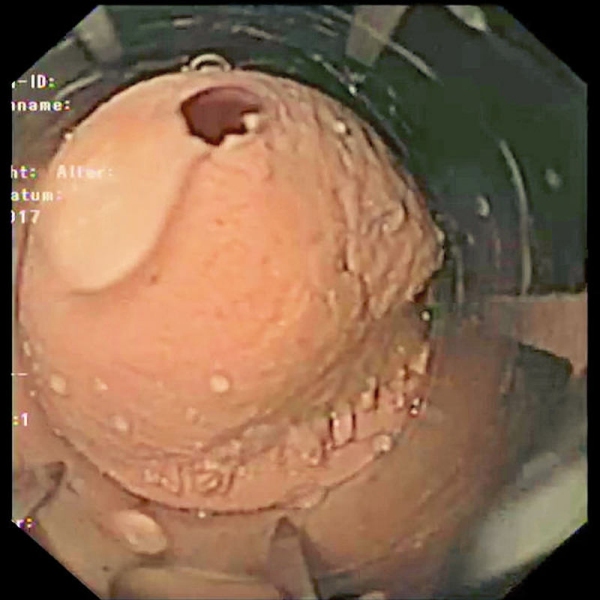

Simulator Gastro združuje možnosti realističnega anatomskega modela in usposabljanja za intervencijsko endoskopijo. Veliko število različnih vložkov omogoča zdravljenje polipov, kot so vbrizgavanje, dvigovanje, rezanje in odstranjevanje, simulacija zaustavitve krvavitve, stentiranje in drugo. Simulator in vložki so izdelani iz popolnoma umetnega materiala.

- Model za usposabljanje za intervencijsko gastroskopijo

- Realistične anatomske strukture

- Odstranjevanje tkiva s hladno zanko, npr. polipektomija

- Odvzem biopsije tkiva s kleščami

- Vadba vbrizgavanja tkiv

- Varikacijska ligatura

- Vstavljanje stentov v požiralnik, želodec in dvanajstnik

- Zdravljenje krvavitev / zaustavljanje krvavitev z injekcijami, sponkami in ligiranjem traku

- Vadba z obstoječimi endoskopi in originalnimi pripomočki